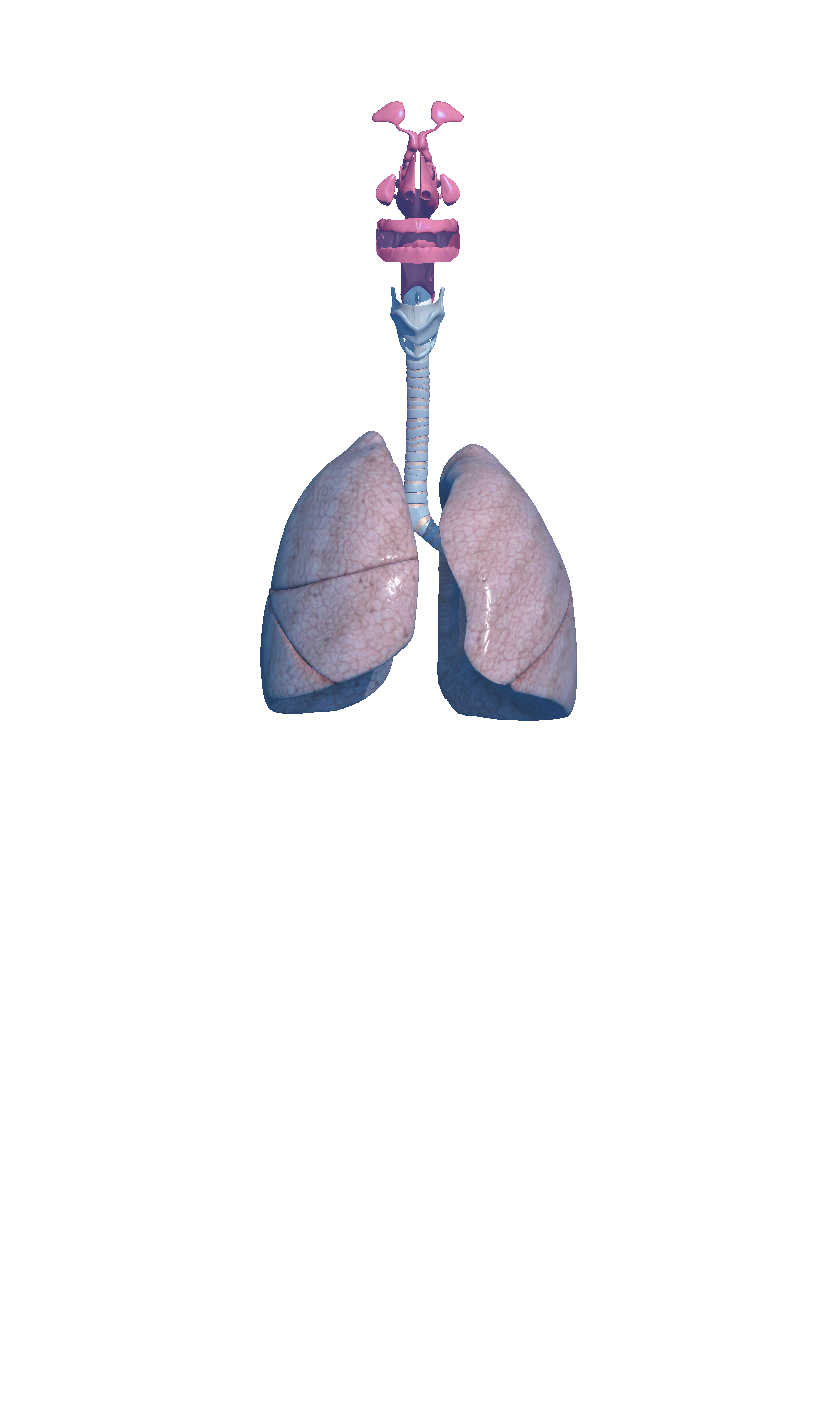

Complete and easy-to-use virtual guide for learning, understanding, and visualizing the complexities of human anatomy in 3D. Includes information and images for each anatomical system and part, multiple options to interact with the 3D anatomy models (hiding, fading, etc), and much more.

We believe that learning by interaction is the best and easiest way to study human anatomy.

- highly detailed

Hi-res imagery everywhere you need it

- Respiratory